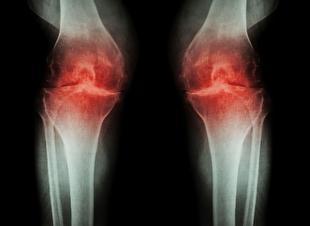

برچسبها:آرتروزجراحیبیماریمیزانلینک اصلی خبر تاریخ انتشار:1404-06-2311:13:49دستهبندی:سایرخبرگزاری:میزانبازدید:4اضافه وزن، انحراف زانو و عفونت، از عوامل اصلی بروز آرتروز زانوفوق تخصص جراحی زانو با اشاره به عوامل بروز آرتروز گفت: صدمه غضروف، افزایش ساییدگی مفصل، اضافه وزن، انحراف زانو و برخی عفونتها میتواند آغازگر این بیماری باشد.ادامه خبر ...اخبار مرتبط صدای انفجار در شمال غرب تهران ناشی از آتش بازی در یک مجتمع تجاری استخبرگزاری مهر - 1404-09-07 در پس همه منازعات، روندی تکاملی در تاریخ روابط بینالملل جریان داردخبرگزاری ایرنا - 1404-09-07 پایان مسابقات جام فجر با قهرمانی وزنهبردار فوقسنگین ایرانخبرگزاری ایسنا - 1404-09-07 تنیس روی میز جوانان جهان؛ کامبک فرجی با شکست حریف آمریکاییخبرگزاری ایرنا - 1404-09-07 پیروزی دانشگاه آزاد و نفت در لیگ برتر واترپلوخبرگزاری مهر - 1404-09-07 کامبک شیرین بنیامین فرجی در قهرمانی نوجوانان جهانخبرگزاری ایسنا - 1404-09-07 رونمایی از برترینهای هفته سوم لیگ برتر تفنگ و تپانچه بانوانباشگاه خبرنگاران جوان - 1404-09-07 قهرمان و ملیپوش سابق ژیمناستیک : باید همه به نقوی کمک کنیم/ فدراسیون ژیمناستیک در مسیر آرامش قرار گرفتخبرگزاری برنا - 1404-09-07 رونمایی از برترینهای هفته سوم لیگ برتر تفنگ و تپانچه بانوانخبرگزاری ایرنا - 1404-09-07